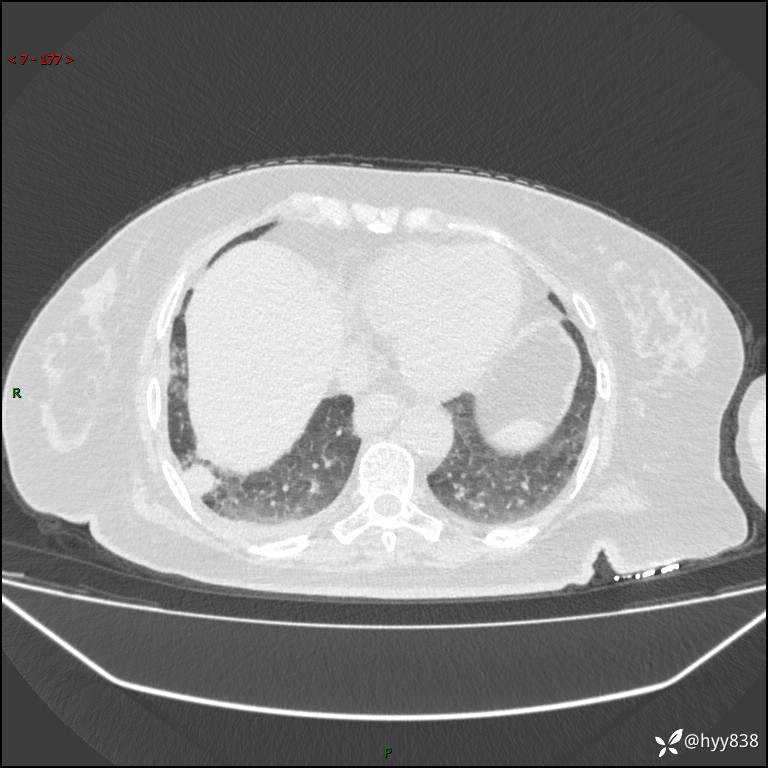

患者性别:女

患者年龄:57岁

简要病史:昏迷入院

胸部 CT平扫、